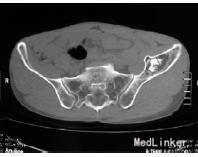

查体:左侧髋关节“4”字实验完成较右侧差,左下肢直腿抬高实验30°。 辅查:腰椎CT:L4/5、L5/S1腰椎间盘突出并左侧隐窝狭窄,相应神经根受压,行髋部X线检查提示左髂骨内占位,进一步行骨盆CT检查提示:左髂骨内可见1大小约4cm×3cm近椭圆形占位性病变,边界清楚,周围骨组织可见厚薄不一的硬化边,其中央有钙化表现,未见骨膜反应,测CT值在-118HU~-129HU之间

诊断:(1)左髂骨占位,脂肪瘤待查;内生软骨瘤待查。(2)腰椎间盘突出症(L 4/5、L5/S1)。 治疗:手术剔除。术中所见:左髂骨内可见1大小约4cm×3cm黄色软组织肿块,表面柔软,边界清楚,肿瘤内可见纤维间隔,中央部分不均匀钙化,与周围骨组织无浸润、骨质无破坏表现,术中诊断左髂骨内脂肪瘤。